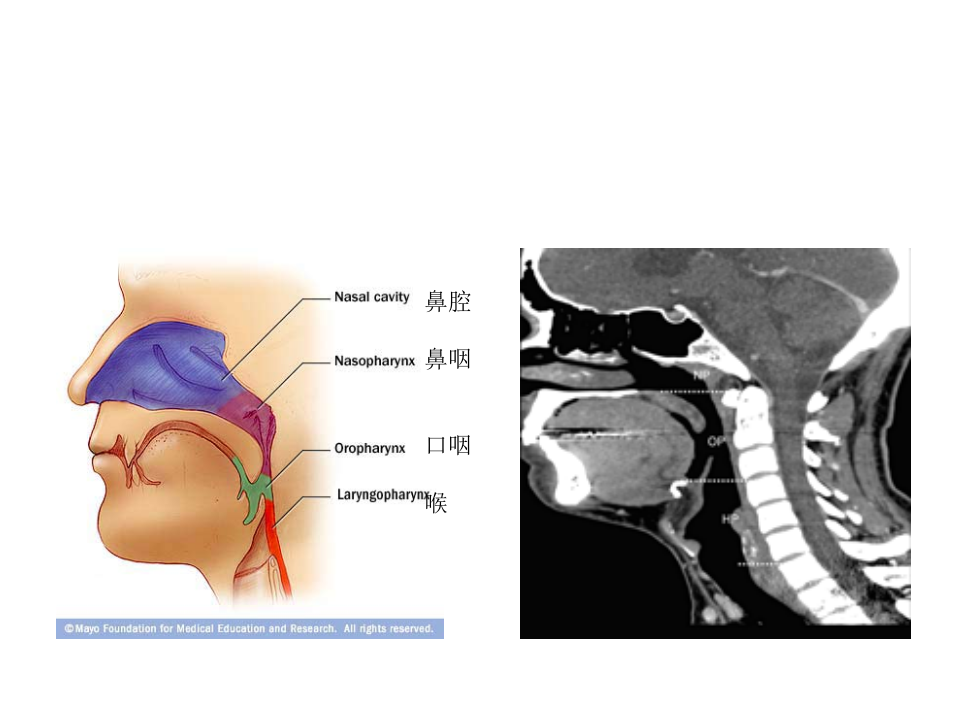

耳鼻喉科

5)咽部解剖、扁桃体炎2015.ppt